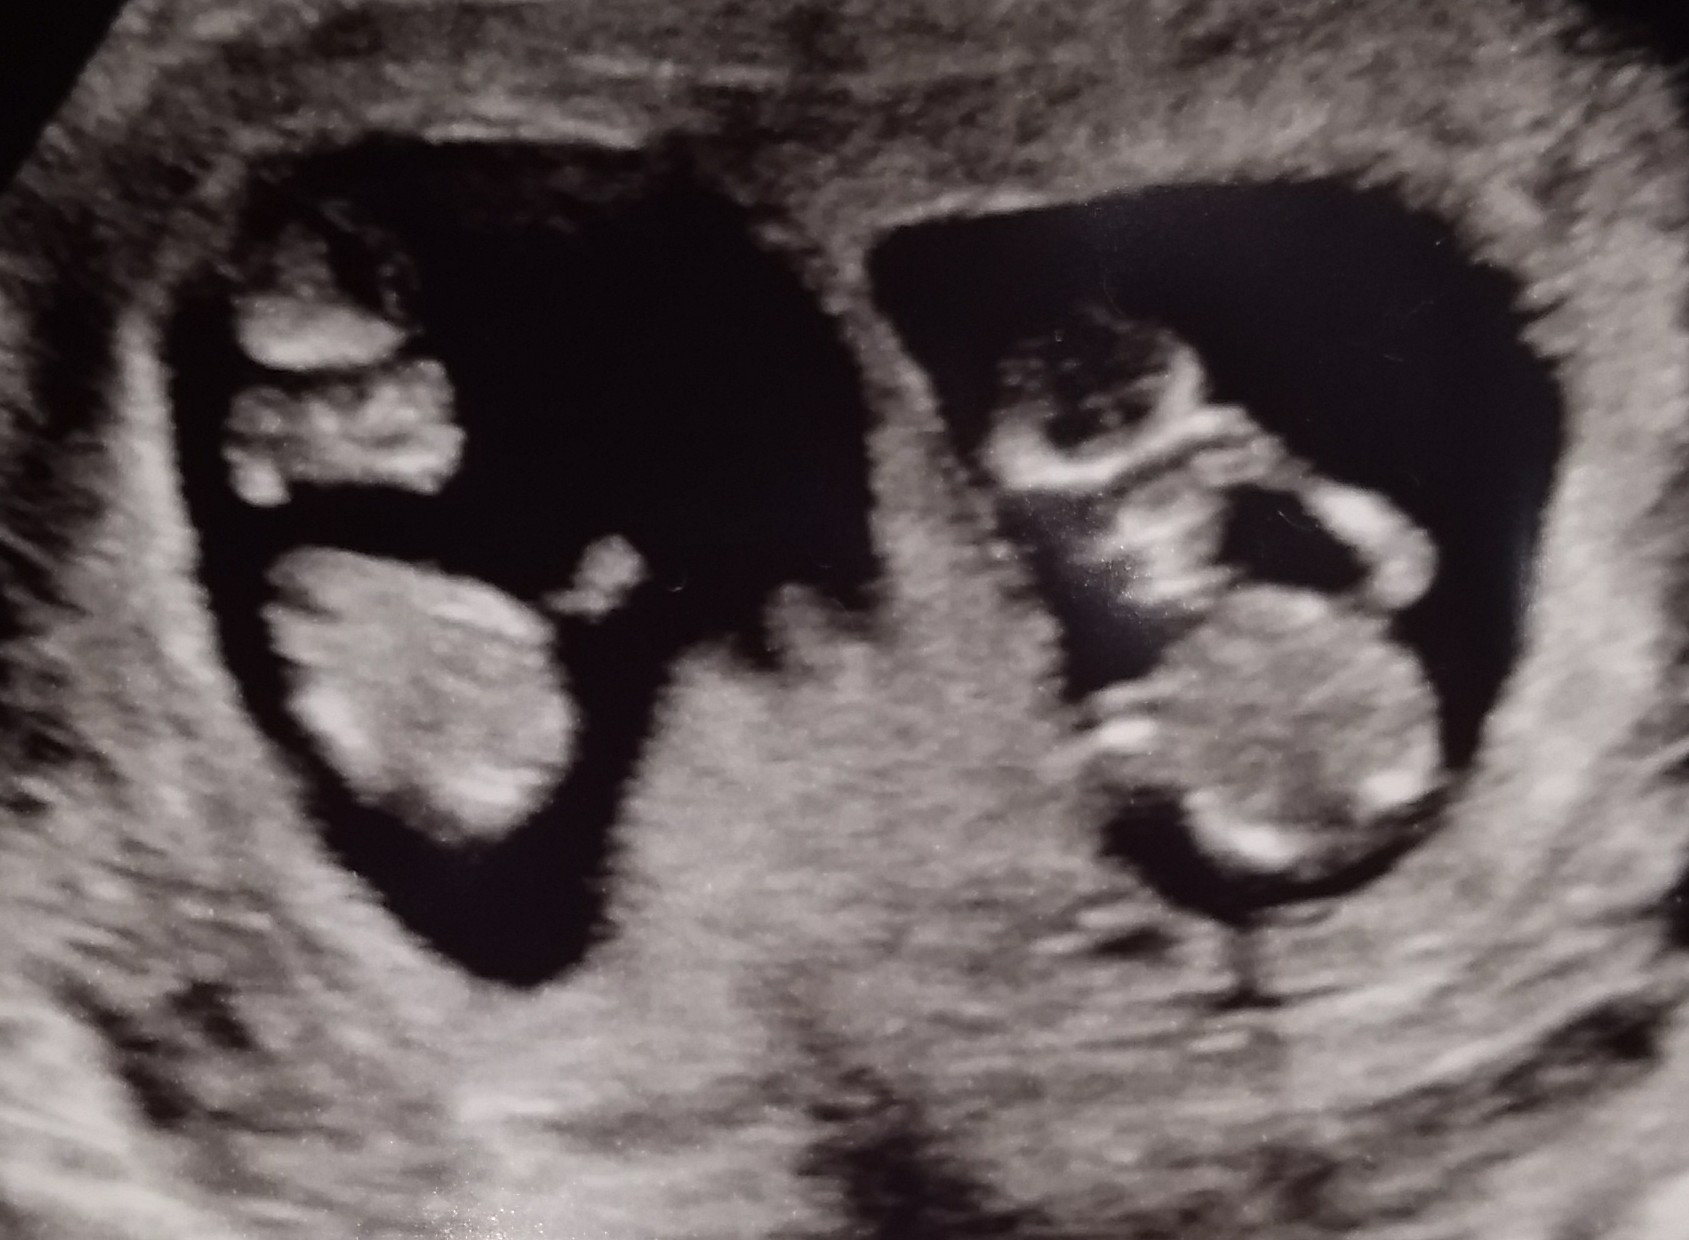

• 12 weeks 4 days!!

• It’s amazing how clear the ultrasounds get at 12 weeks!